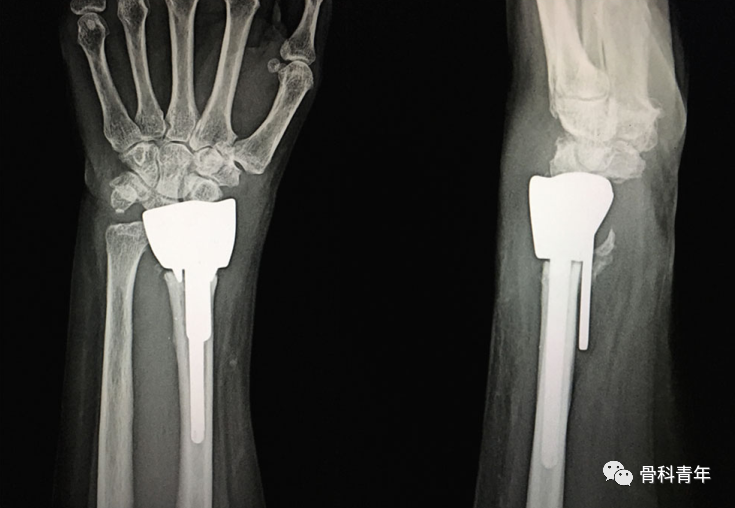

髓内钉技术广泛应用于长骨骨干骨折,闭合或有限切开复位有效降低医源性因素对血运的破坏,并具有良好的轴心固定生物学优势。桡骨远端髓内钉出现较晚,该技术适用于完全关节外骨折及简单的关节内骨折,对关节内粉碎骨折并不适用。

桡骨远端骨折髓内钉固定的前提是闭合复位效果满意,克氏针临时固定后,通过桡骨茎突开口,自腕背侧第1/2间室间隙进入。该技术存在潜在的损伤包括桡神经分支损伤,螺钉穿入下尺桡关节或桡腕关节等。